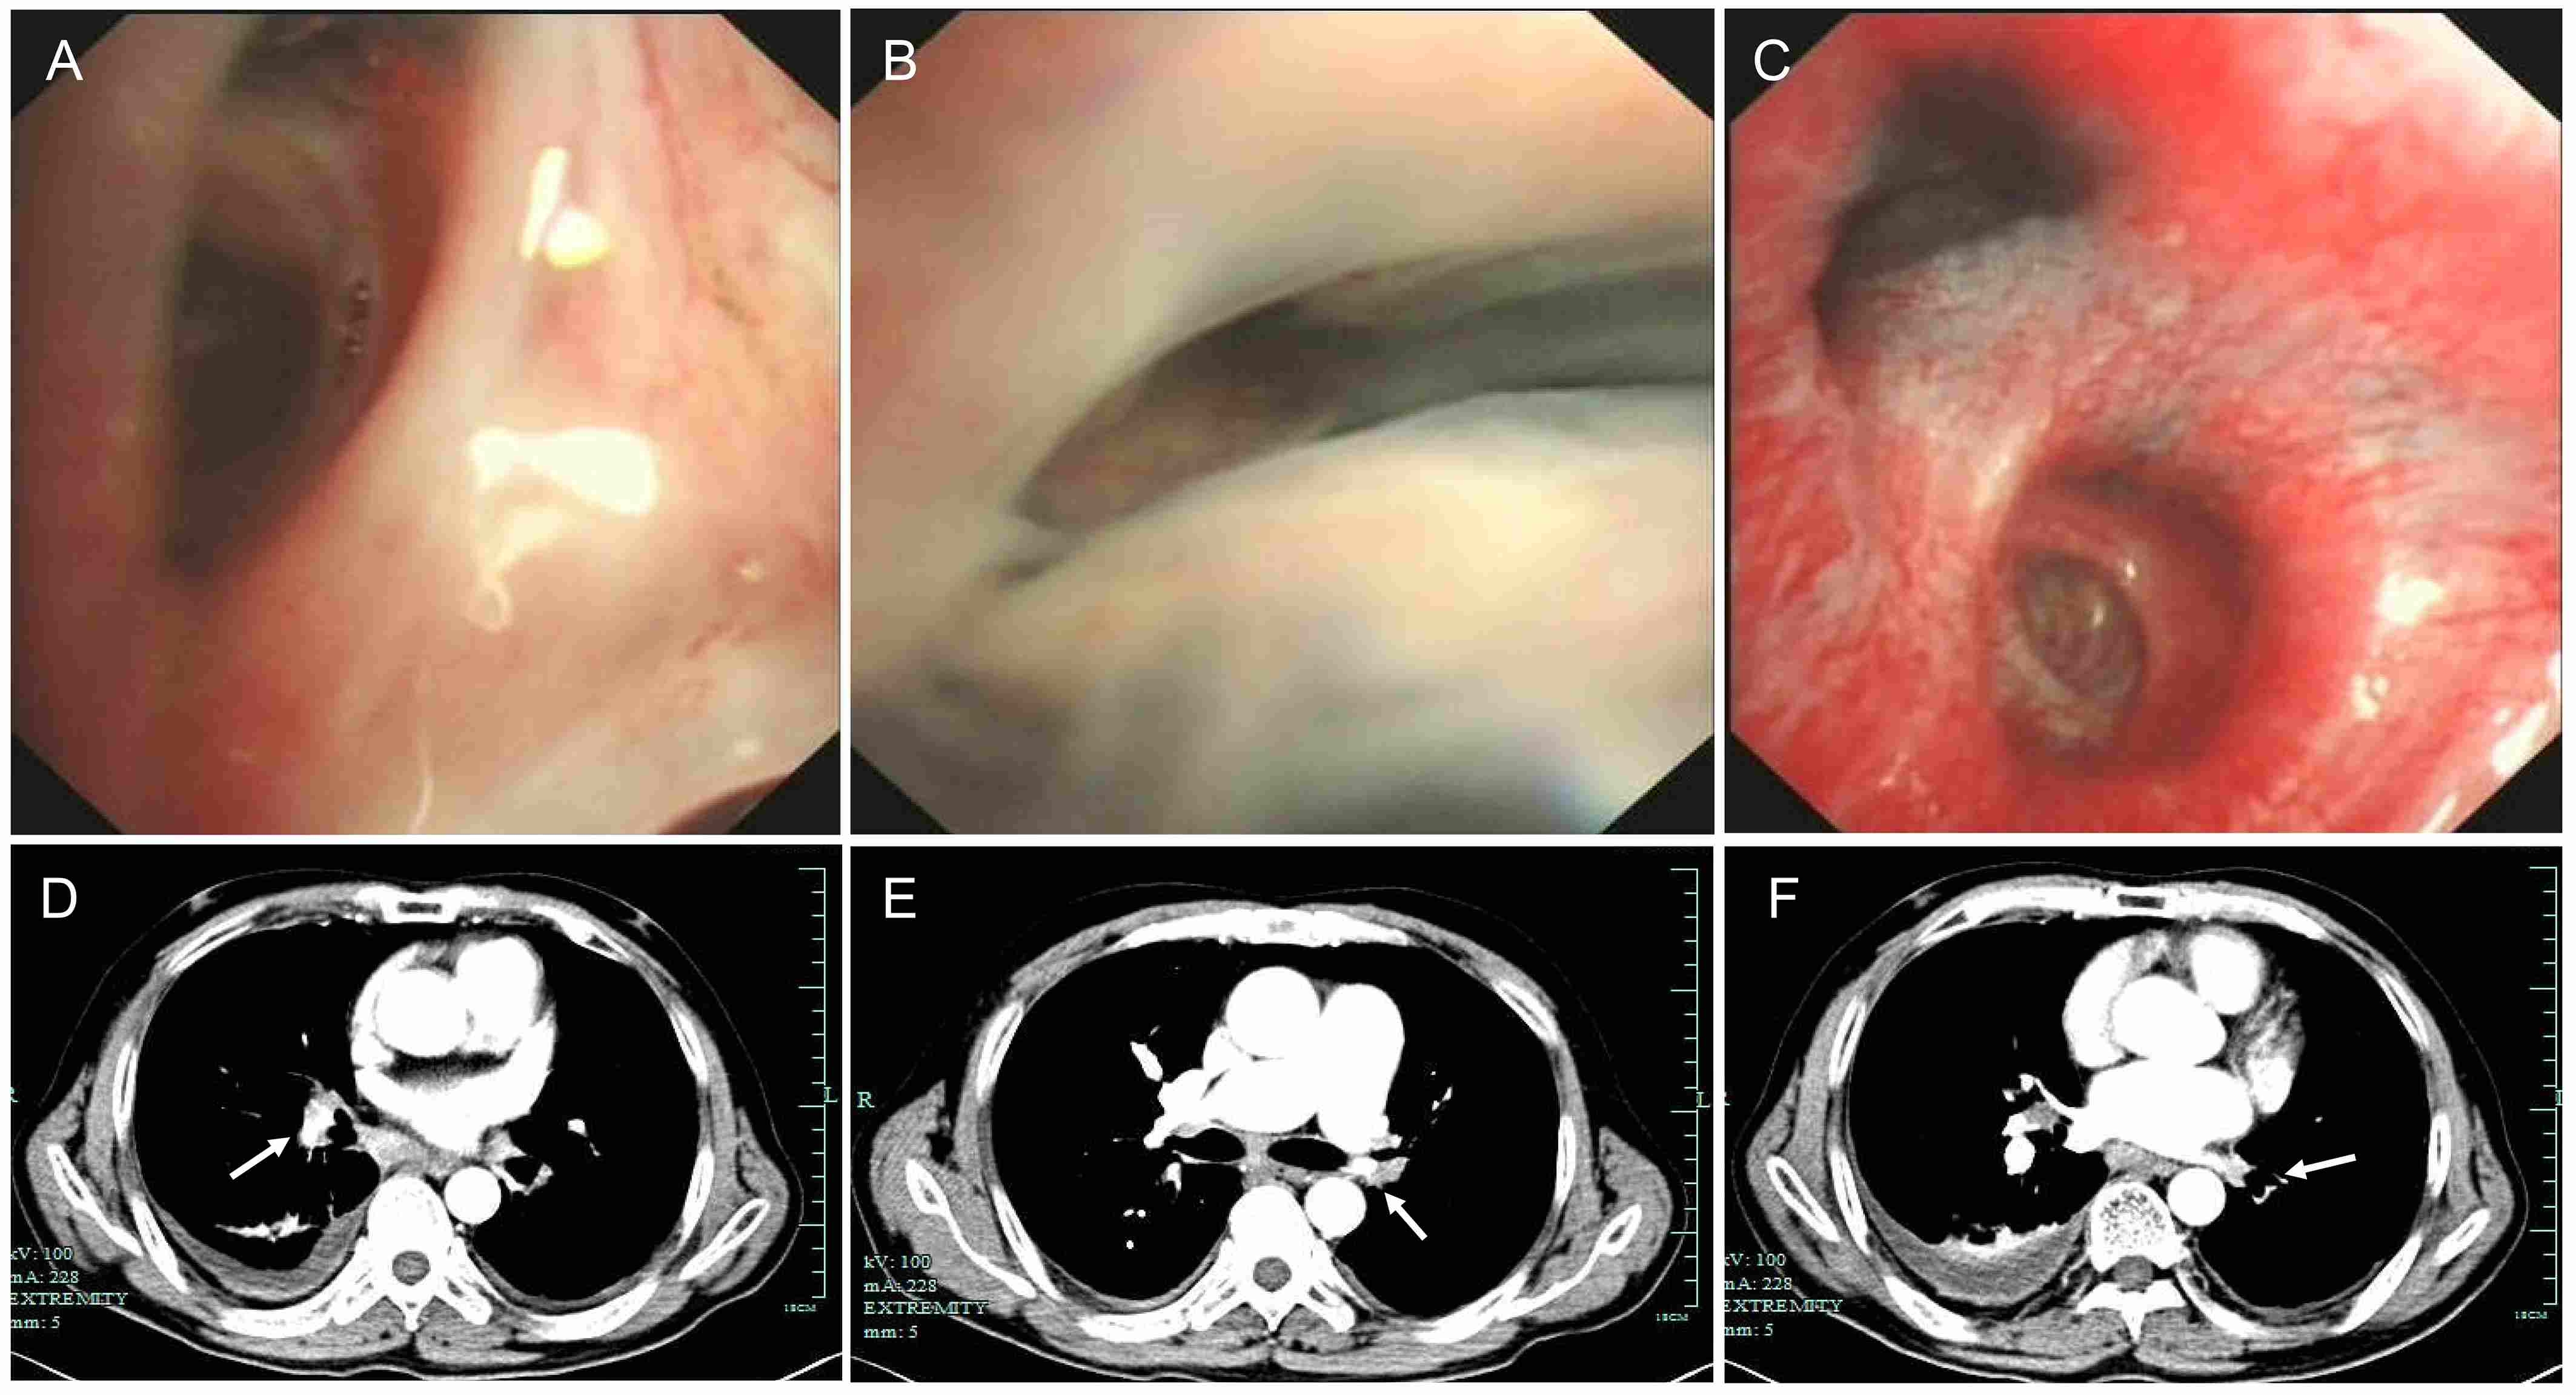

Abstract Body (Do not enter title and authors here): Introduction:Fibrosing mediastinitis is a rare condition characterized by excessive fibrous tissue proliferation in the mediastinum, leading to compression of vital structures. We present a case of idiopathic fibrosing mediastinitis with progressive pulmonary hypertension and multi-vessel stenosis, highlighting diagnostic challenges and management strategies. Research Questions: The case explores the clinical and imaging features of fibrosing mediastinitis, its differentiation from other causes of pulmonary hypertension, and the potential treatment options for fibrosing mediastinitis-related vascular obstruction. Aims: This case aims to (1) describe the clinical course and diagnostic pitfalls in a patient with long-standing fibrosing mediastinitis, (2) evaluate the role of imaging and invasive testing in diagnosis, and (3) assess the efficacy of endovascular stenting in symptomatic relief. Methods: A 58-year-old male with a 5-year history of recurrent dyspnea and chest tightness underwent serial evaluations, including CT angiography, echocardiography, pulmonary function tests, bronchoscopy, and right heart catheterization. After failing medical therapy, he underwent percutaneous pulmonary artery stenting. Results: Imaging revealed mediastinal lymphadenopathy with calcification, pulmonary artery stenosis, and tracheobronchial compression. Pulmonary arteriography confirmed severe stenosis in multiple pulmonary arteries. Stent implantation improved exercise capacity (6-minute walk distance: 360m to 485m) and oxygen saturation. Conclusions: Fibrosing mediastinitis is a rare but treatable cause of pulmonary hypertension. A high index of suspicion is needed in patients with progressive dyspnea and mediastinal fibrosis. Endovascular stenting may provide symptomatic relief in select cases, though long-term outcomes require further study.